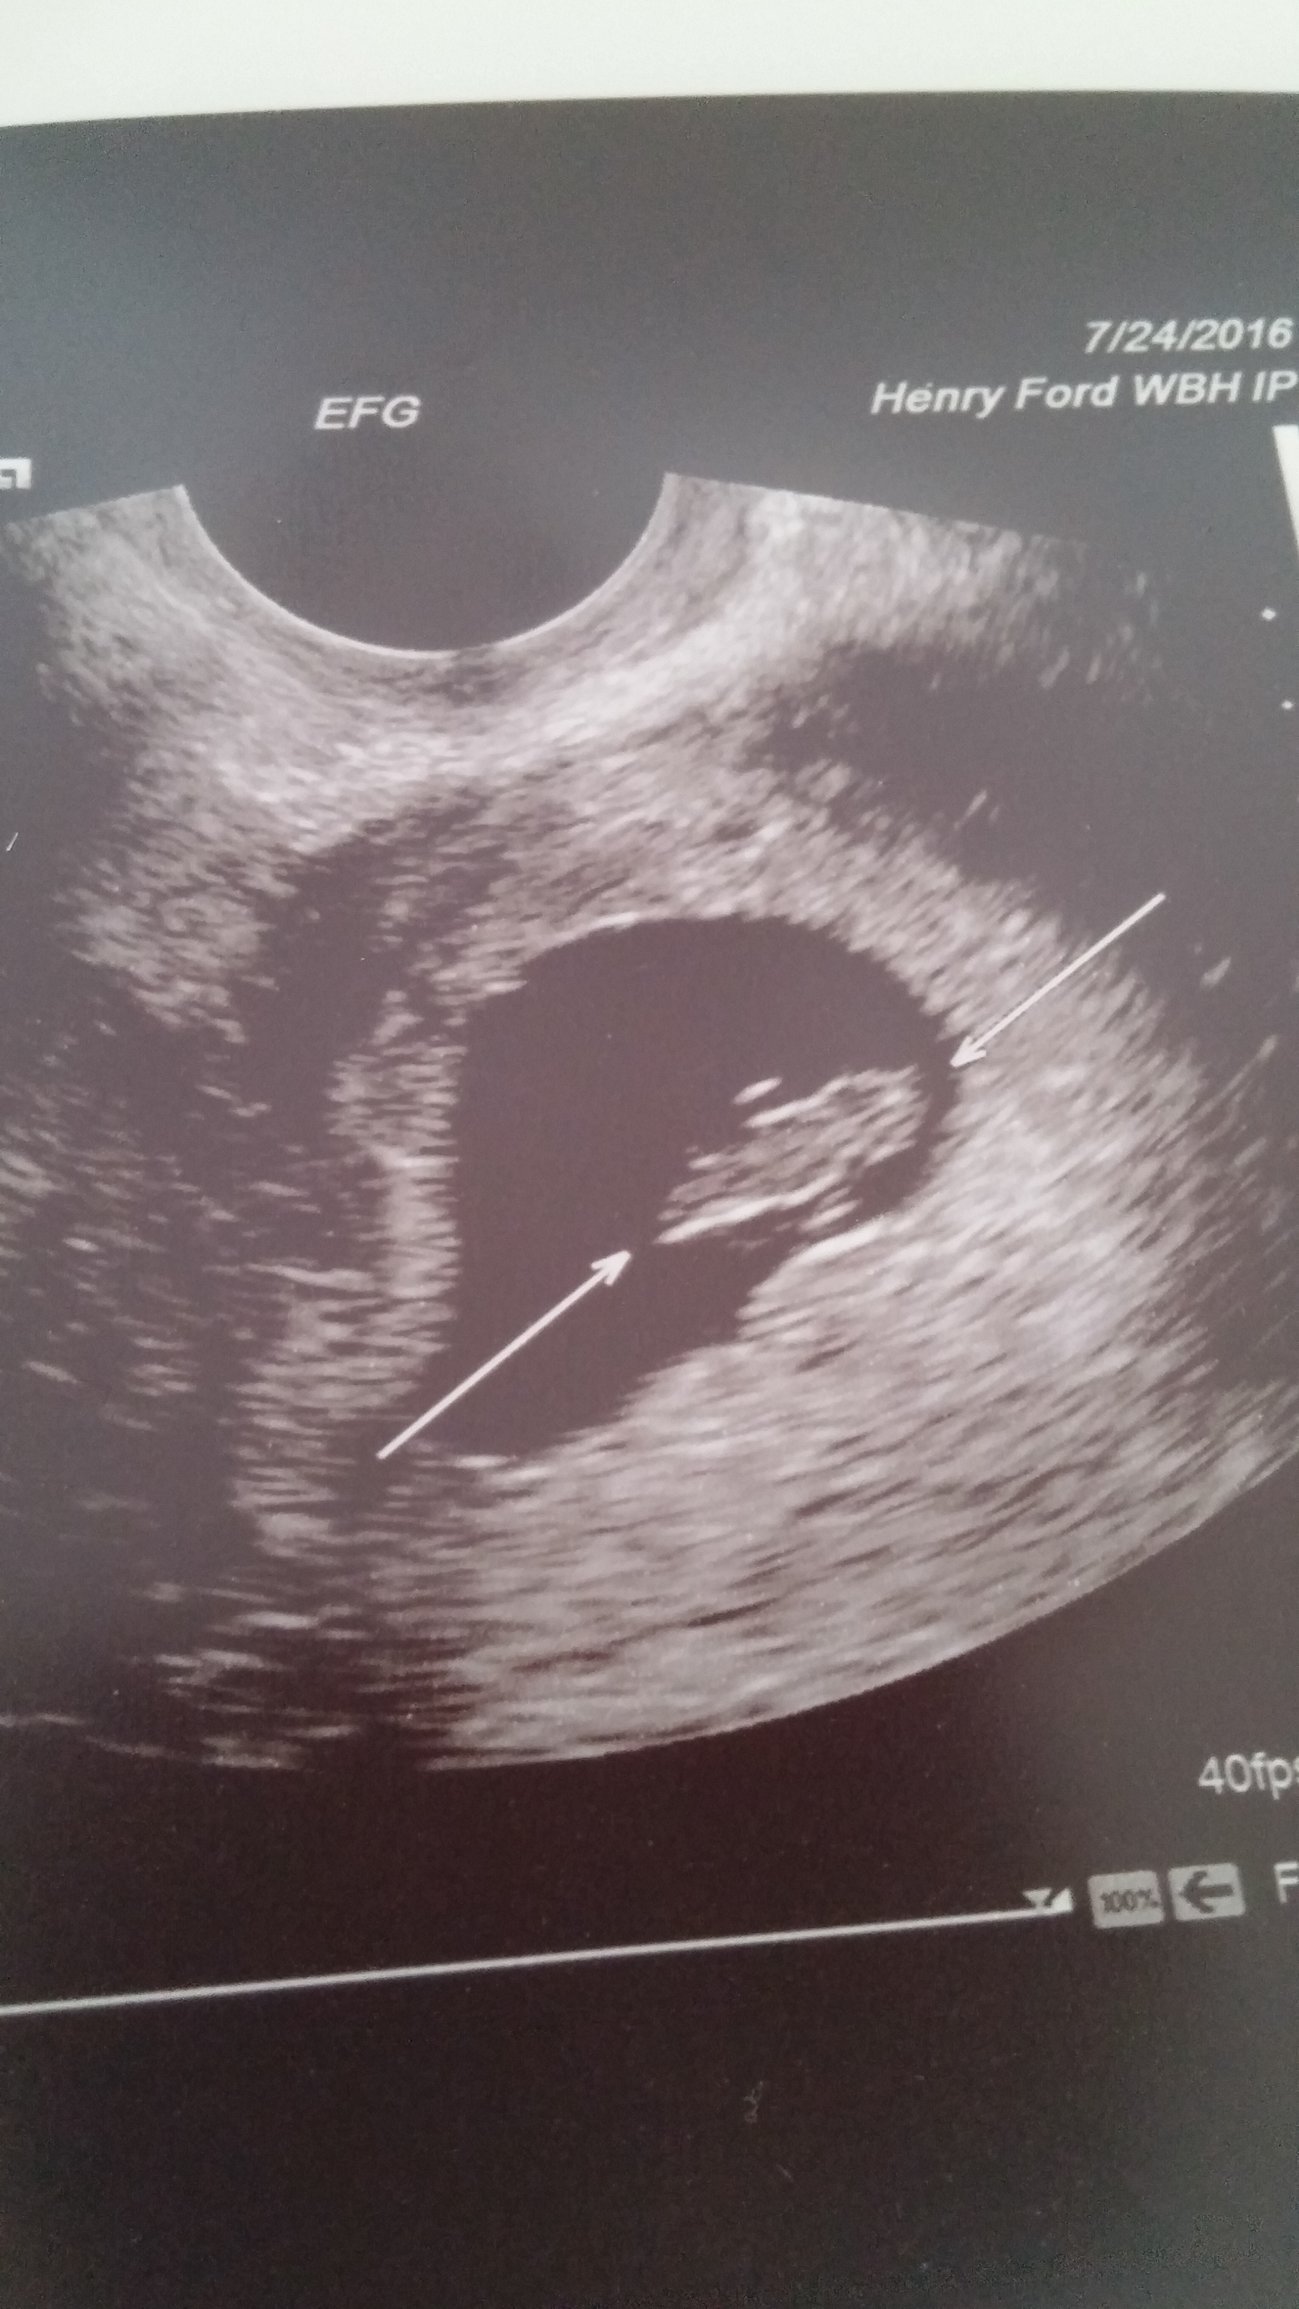

hi everyone! Thanks for all the best wishes! sooooo we heard the heart beats and...... 7 weeks exactly and we were beyond beyond beyond surprised when... She told us oh I see 2.... Wow I'm still in shock and *healthy and happy two little beans please* twins does not run in our families

little thing 2(B) is hiding a bit. So nervous y'all!!!! So surprised. Little miracles beans *healthy and happy*

7 weeks. She was zoomed in pretty tight to try to see a membrane. She's worried they are mono-mono since they are so close, but I know it's too early to see it